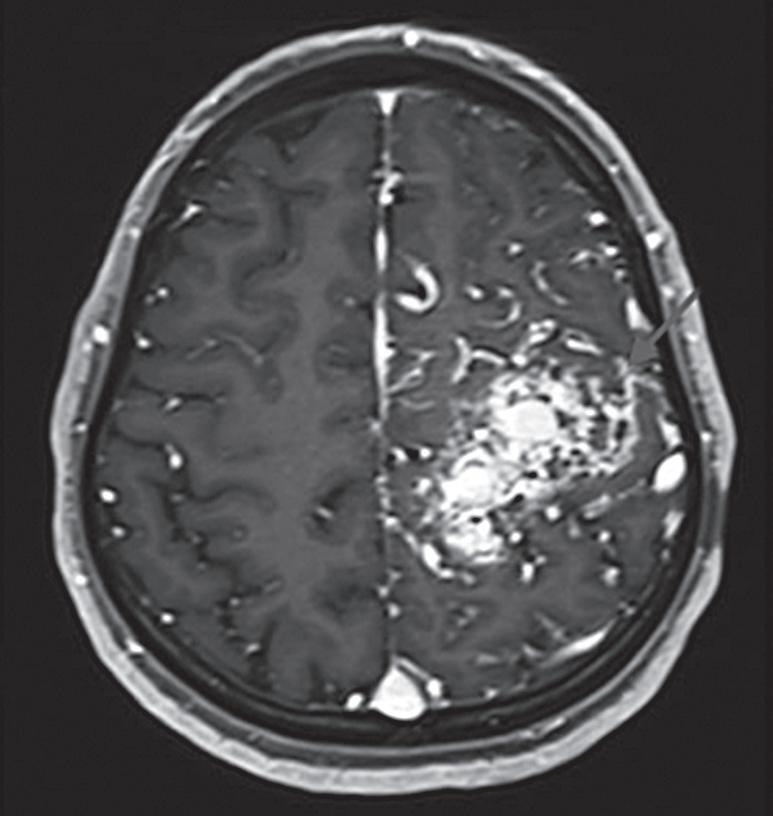

Fig. 1-16. RNM encéfalo T1 com contraste: (a) Coronal e (b) axial demonstrando MAV grau 4 frontoparietal esquerda. (c,d) Arteriografia cerebral AP mostrando a irrigação pelos ramos da cerebral anterior e média esquerda, além da cerebral anterior direita, com drenagem superficial para o seio sagital superior. Seta azul apontando para o nidus da MAV.

Fig. 1-17. RNM encéfalo T1 com contraste (a) axial e (b) T2 sagital demonstrando MAV grau 5 profunda temporoinsular esquerda com extensão nos núcleos da base. (c,d) Arteriografia cerebral,demonstrando a drenagem venosa profunda para veia cerebral interna (seta azul) com sinais de hipertensão.